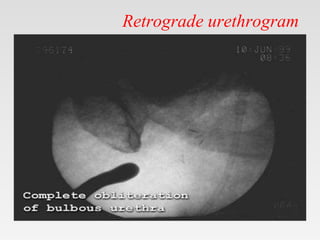

• Retrograde urethrogram

• Antegrade cystourethrogram

Retrograde urethrogram